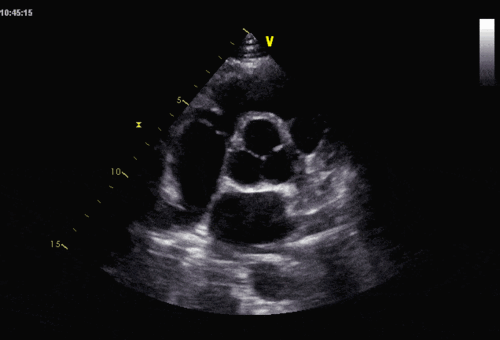

超声可以评估二尖瓣前叶的活动,反应sam征,以了解左室流出道梗阻情况

肥厚型心肌病超声心电图

5 平方厘米 室间隔明显增厚者,二尖瓣可出现sam征,心尖区可闻及收缩